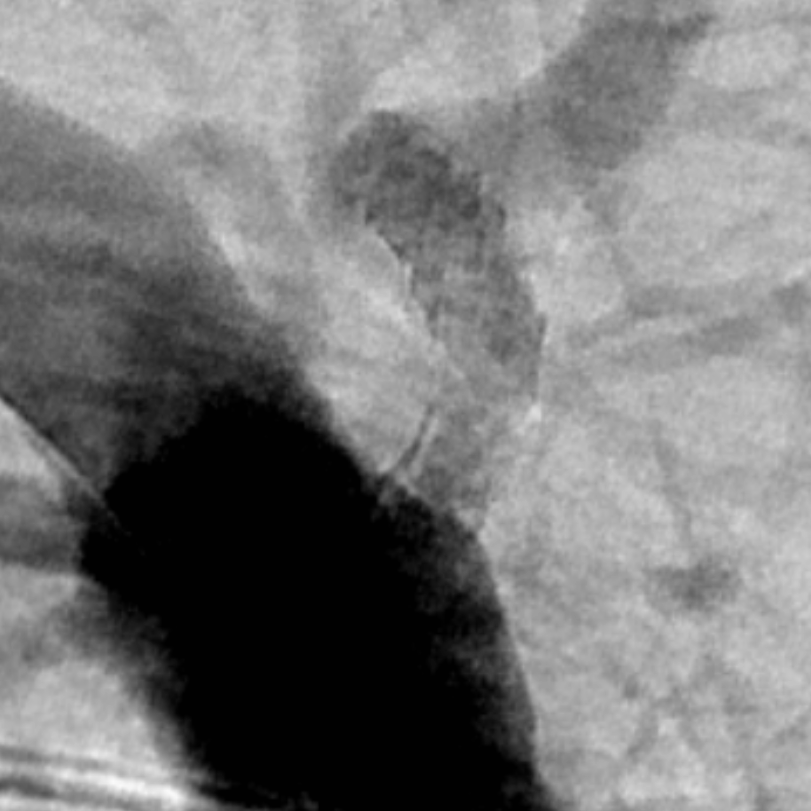

今日話題:在跳動的血管當中精準植入支架消除椎動脈開口狹窄

今日話題:在跳動的血管當中精準植入支架消除椎動脈開口狹窄?椎動脈開口狹窄看似是一個簡單的手術。但是,要把這個手術做好,也絕非易事。實戰(zhàn)花絮:支架的下緣猶如刀切樣置于血管壁的上緣(圖4-6),是我們追求的目標之一